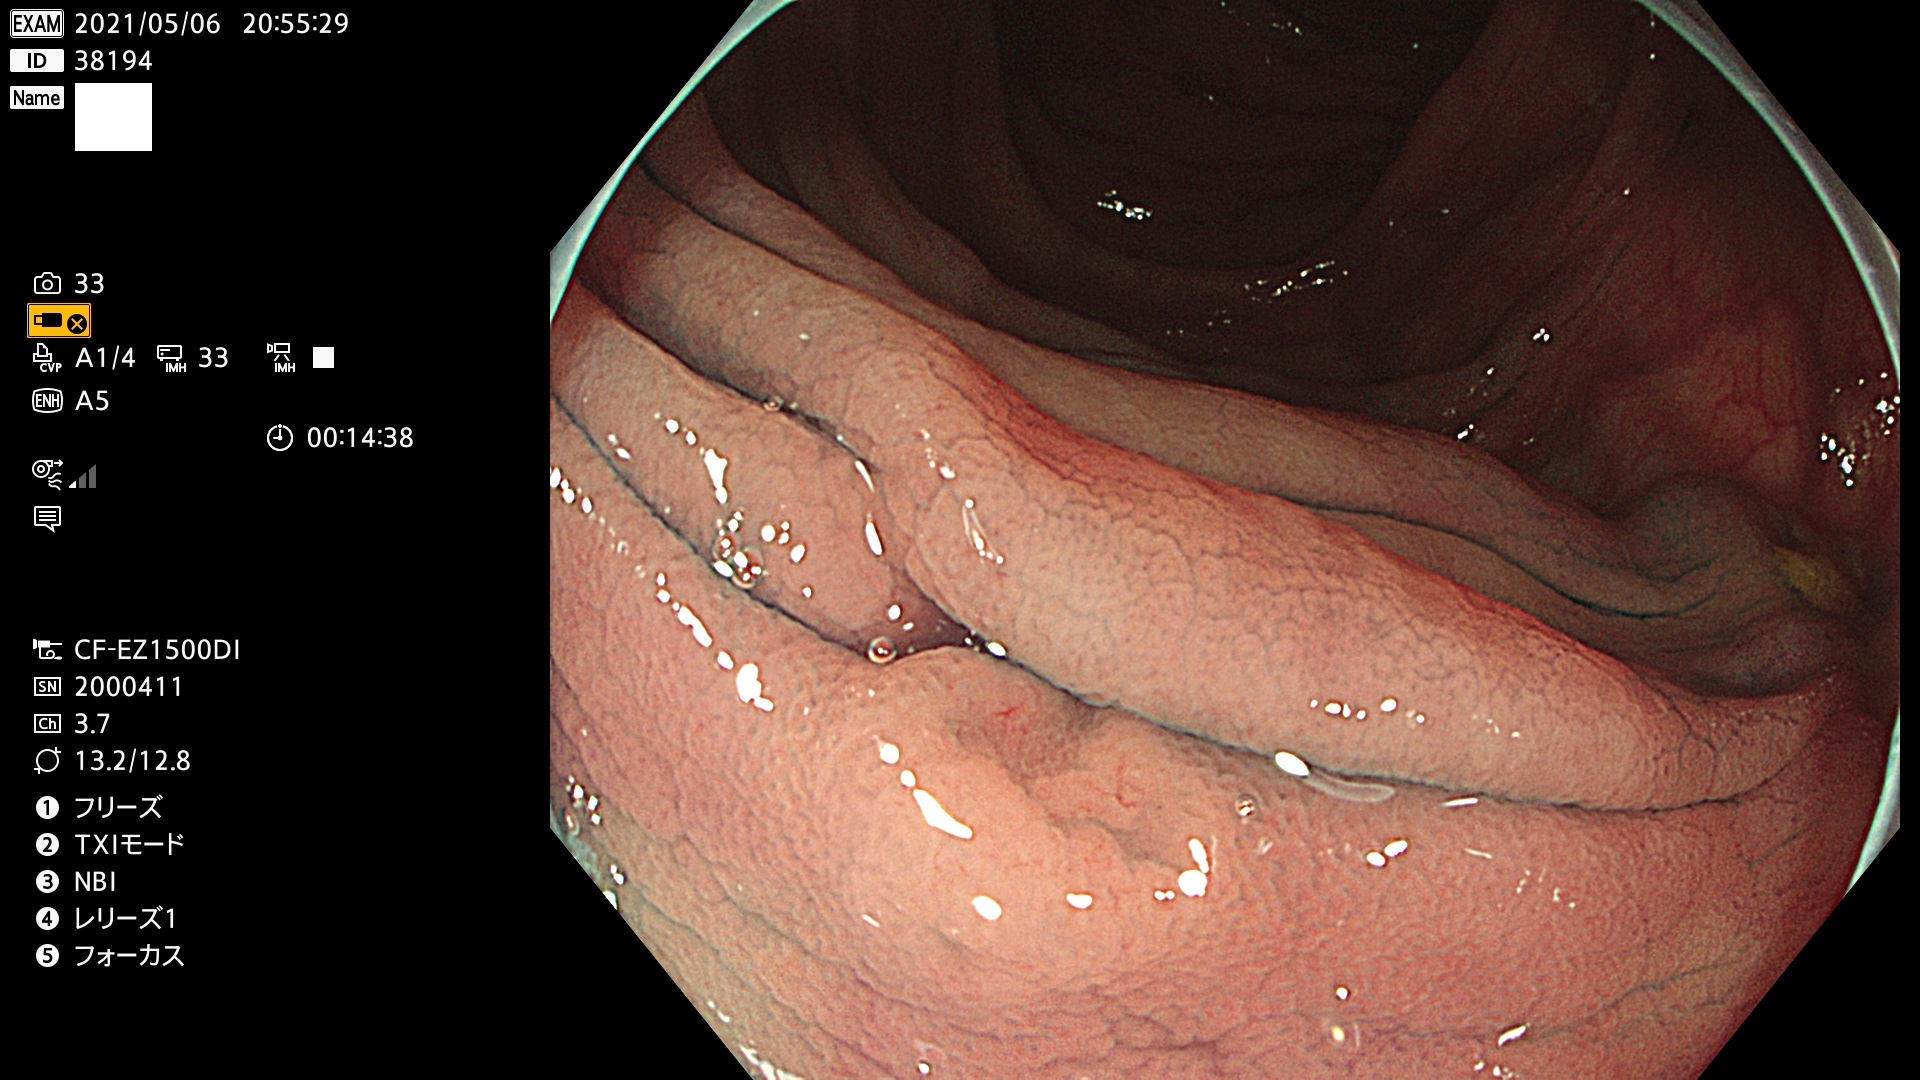

腺腫発見率 72 % (カルテ番号 38100〜38199の100名の方の検査結果で集計)大腸癌検診最新情報

以下のカルテ番号の方に腺腫(Adenoma,Group3〜5)が見つかりました(集計法)

38101 38103 38104 38106 38107 38108 38109 38110 38111 38112 38113 38114 38115 38117 38118 38122 38123 38124 38125 38126 38127 38128 38130 38131 38132 38135 38137 38138 38140 38141 38142(SSAPのみ) 38143 38144 38145 38146 38147 38148 38149 38150 38151 38152 38153 38154 38157 38158 38160 38161 38162 38164 38165 38166 38167 38168 38169 38172 38176 38177 38178 38181 38182 38183 38184 38187 38189 38190 38191 38192 38193 38194 38195 38196(SSAPのみ) 38198

発見困難で危険性の高い平坦型病変(上記100名より抽出) ![]()